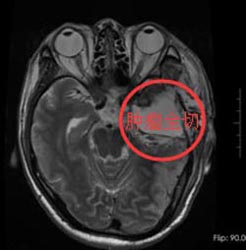

经家属同意后,由鲁主任主刀在唤醒麻醉下行“左侧颞叶占位性病变切除手术”。术前导航定位右颞肿瘤组织,术中给予唤醒麻醉,电生理监测运功中枢,避开功能区,术中快速病理检查考虑Ⅱ级胶质瘤,继续显微镜下分块切除,术中出血量少,过程顺利。术后病检结果与术前诊断相符。

手术后